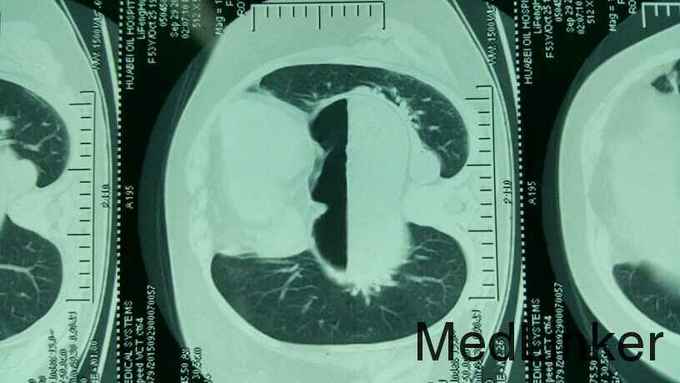

反酸、烧心、活动后胸闷气促、哮喘20年,左季肋部疼痛伴呕吐3月

诊断:食管裂孔疝、胃食管反流病 治疗:行腹腔镜食管裂孔疝修补加胃底折叠术

该病例的裂孔疝巨大,大部分胃疝入胸腔,之所以经过这么长时间未被诊断出来,主要原因有以下两点: 1、患者既往虽有反酸烧心病史,但症状并没有特别严重,容易被患者当普通胃病忽视;2、患者活动后胸闷气促、哮喘症状实际上与巨大裂孔疝压迫胸腔有关,但一直被误诊为过敏性哮喘治疗,医生并没有讲哮喘症状和反流症状联想在一起,从而忽视了胃镜、上消化道造影、CT等检查排除胃食管反流和食管裂孔疝,从而长期误诊为哮喘而得不到彻底治疗。此次因为患者出现呕吐、左季肋部疼痛才想到做进一步检查发现巨大裂孔疝。 术后患者所有症状都消失,包括活动性胸闷气促的症状。该病例患者最大的收获不是呕吐和腹痛止住了,而是长达20年的所谓哮喘好了,病人感到是意外收获。这个病例提醒大家在临床上遇到不典型的哮喘患者,一定多做鉴别诊断,要考虑到胃食管反流和食管裂孔疝的可能。